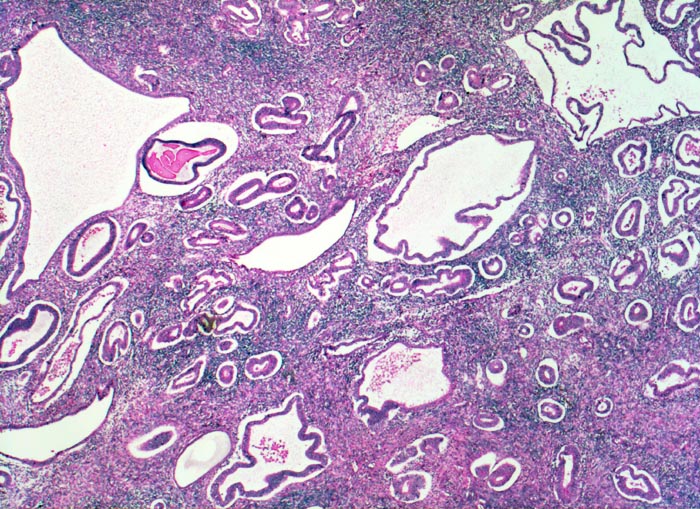

• Hyperplasie mit Atypie (AH)/Endometrioide intraepitheliale Neoplasie (EIN) Die hyperplastische Mukosa ist verdickt (2-3cm statt normal 0.2-1.2cm), homogen-weisslich glasig und weich. Die Drüsen sind verstärkt verzweigt, zystisch transformiert und ausgekleidet von mehrreihigem Epithel. Bei der Hyperplasie beträgt das Drüsen-Stroma Flächenverhältnis >1:1. Die Vorstufe der Hyperplasie mit gleichartigen architektonischen Veränderungen aber einem Drüsen-Stromaverhältnis <1:1 bezeichnet man als unregelmässig proliferiertes Endometrium. 1-3% der Frauen mit einer Hyperplasie des Endometriums ohne Atypie entwickeln im Verlauf ein gut differenziertes endometrioides Adenokarzinom. Das Risiko für die Entwicklung eines endometrioiden Adenokarzinoms ist dagegen viel höher bei Vorliegen einer Hyperplasie mit Atypie (> 1074) (> 1075) oder einer endometrioiden intraepithelialen Neoplasie (=Präneoplasie) (> 10369). Bei einem Viertel bis einem Drittel der Patientinnen mit solchen Läsionen in der Kurettage wird in der nachfolgenden Hysterektomie oder innerhalb eines Jahres die Diagnose eines endometroiden Adenokarzinoms gestellt. Das Karzinomrisiko ist 14x erhöht bei der atypischen Hyperplasie bis 45x bei der EIN. In Einzelfällen kann die Abgrenzung einer atypischen Hyperplasie oder einer EIN von einem Karzinom am Kurettagematerial sehr schwierig sein. Beim invasiven Karzinom sind die Drüsenarchitekturstörungen ausgeprägter und zwischen den Karzinomdrüsen fehlt das Stroma stellenweise vollständig.

• Hoch aufgebaute Mukosa.

• Das Verhältnis von Stroma und Drüsen ist zu Gunsten der Drüsen verschoben (Drüsen:Stroma>1:1).

• Die architektonische Komplexität der Drüsen ist in den meisten Fragmenten gering. Viele Drüsen sind zystisch dilatiert oder verzweigt. Keine kribriformen Strukturen.

• Proliferierendes ein- oder mehrreihiges Epithel mit länglichen hellen Kernen und Mitosen.

• Einige Drüsen werden von metaplastischem tubarem Epithel oder Flimmerepithel ausgekleidet. Das sollte der Kliniker dem Pathologen mitteilen: